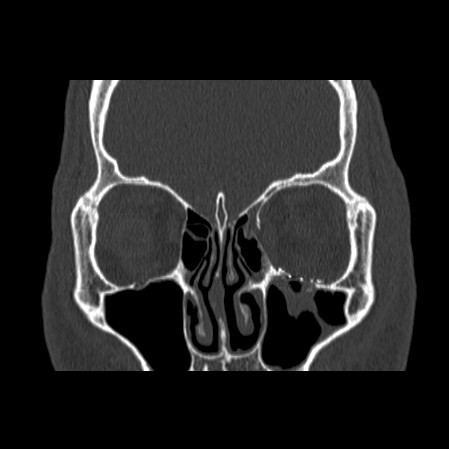

Facial Fracture X-Rays